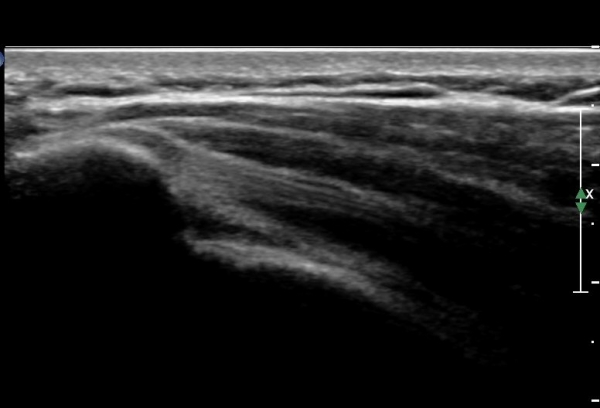

¿À±¸µ¹±â°ßºÀÀδë Á¾´Ü¸é°Ë»ç¿¡¼­ ÀÎ´ë ½ÉÃþ¿¡ ¼ö¾×Àú·ù°¡ °üÂûµÊ(»çÁø 1, 2)

ÀÌ´Â Ãæµ¹ÁõÈıºÀ» ¾Ï½ÃÇÏ´Â ¼Ò°ßÀÓ.